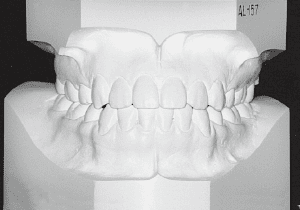

22 After treatment 2-10-’99 17 years 7 month

23 After Retention 1-22-’01 19 years 6 month

Although early treatment improved the slight deviation observed during the deciduous dentition stage, it became apparent that the deviation increased with age, eventually exceeding the limits of treatment. This appears to be an innate deviation, and the developmental pattern observed in this case seems to disregard the occlusion. Four first premolars were extracted (15), crowding was corrected and space closure was performed (16), and surgical intervention improved the deviation (17).